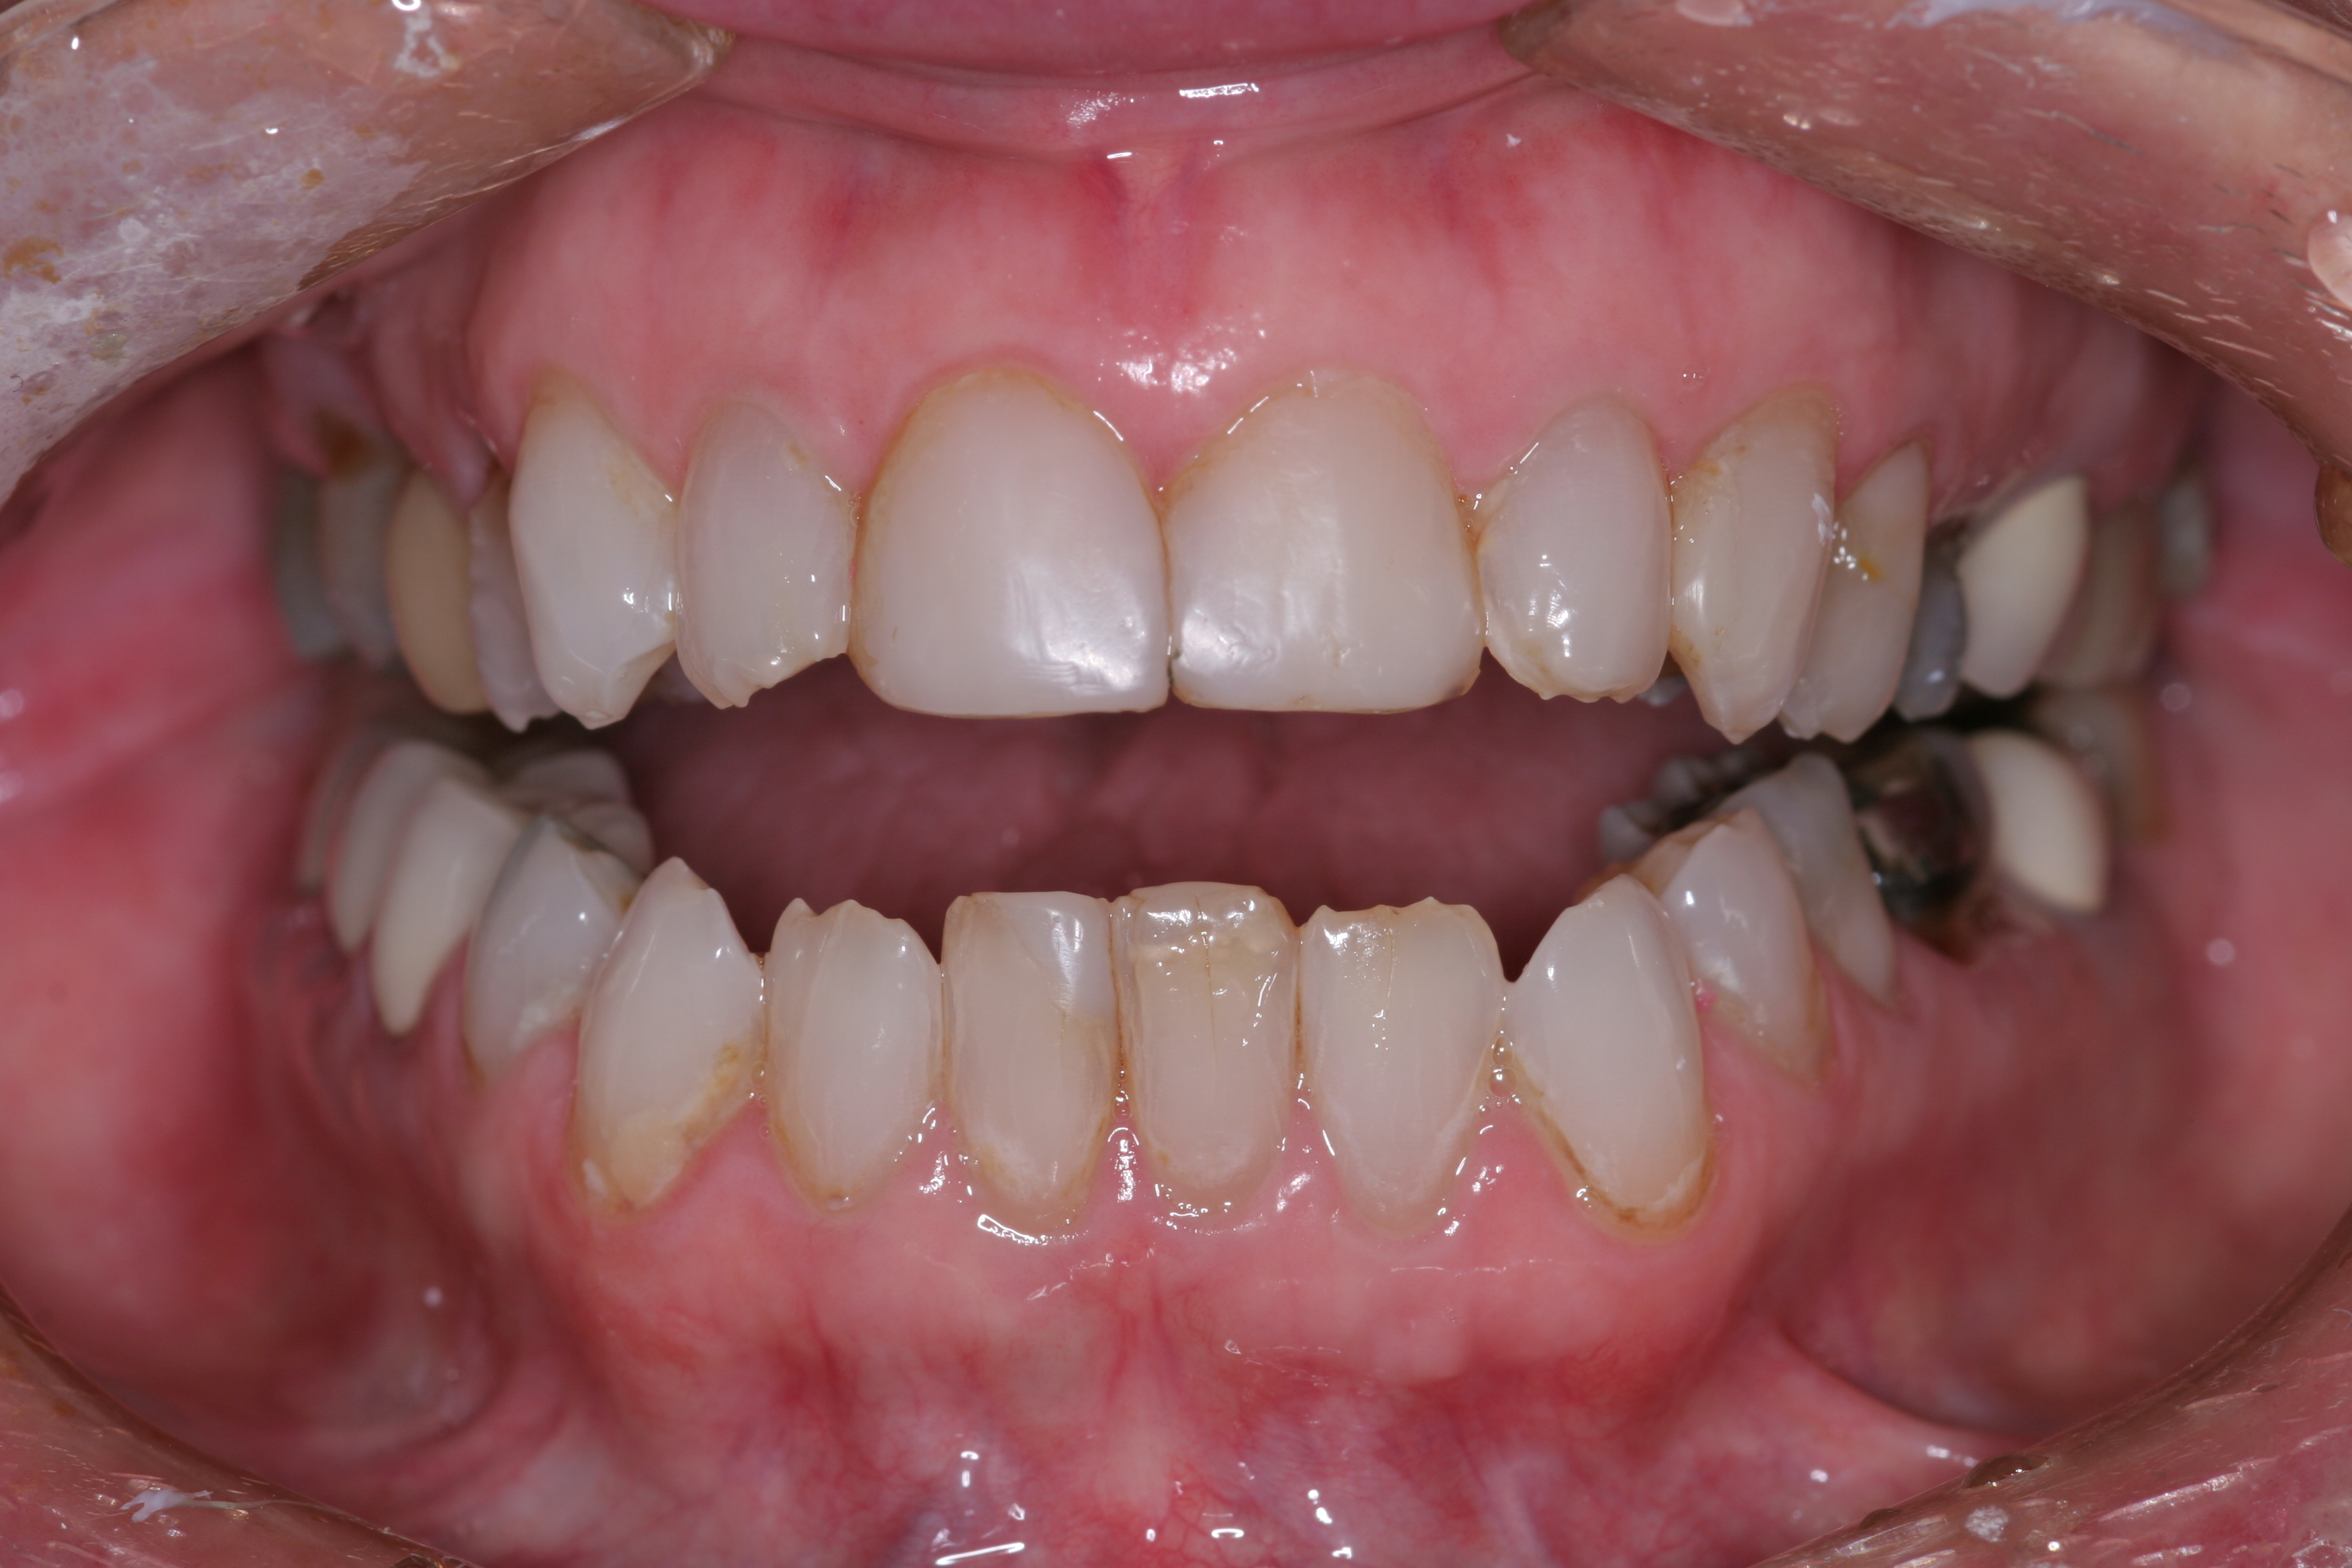

A patient presented with advanced generalized wear of her anterior teeth (Figure 10 and Figure 11). She was displeased with their overall appearance because of their color and wear (Figure 12). A complete examination was performed, revealing instability in her temporomandibular lateral poles bilaterally, sore muscles of mastication, advanced wear, a CR/MIP discrepancy, and loss of her anterior guidance due to the wear. Although the topic is beyond the scope of this article, the patient was also screened for possible sleep apnea. This included an evaluation of the Mallampati score, previous sleep therapy evaluation or treatment, snoring history, an evaluation of her neck size, her weight status, and the presence of the tonsils and their size. In every case, if this clinician suspects airway obstruction to be playing a role in tooth wear issues, the patient is referred to a sleep physician. The patient in this case displayed few apnea risk factors, and the patient’s anterior wear facets fit together like a “lock and key” pattern seen in parafunctional activity. Splint therapy was initiated to stabilize the joints and muscles. A repeatable CR position was verified through load testing. At this point diagnostic models, photographs, a CR bite record, and a facebow were taken and recorded.

(11.) A patient presented with advanced generalized wear of her anterior teeth, and was displeased with their overall appearance because of their color and wear.

Figure 11

(12.) A patient presented with advanced generalized wear of her anterior teeth, and was displeased with their overall appearance because of their color and wear.

Figure 12

(17.) The esthetic, functional, and phonetic changes were evaluated and confirmed in the provisional restorative phase.

Figure 17

(18.) The provisional restorations show the vertical and horizontal changes in the incisal edge position.

Figure 18

(19.) The provisional restorations show the vertical and horizontal changes in the incisal edge position.

Figure 19

(20.) The provisional restorations show the vertical and horizontal changes in the incisal edge position.

Figure 20

(21.) The provisional restorations show the vertical and horizontal changes in the incisal edge position.

Figure 21